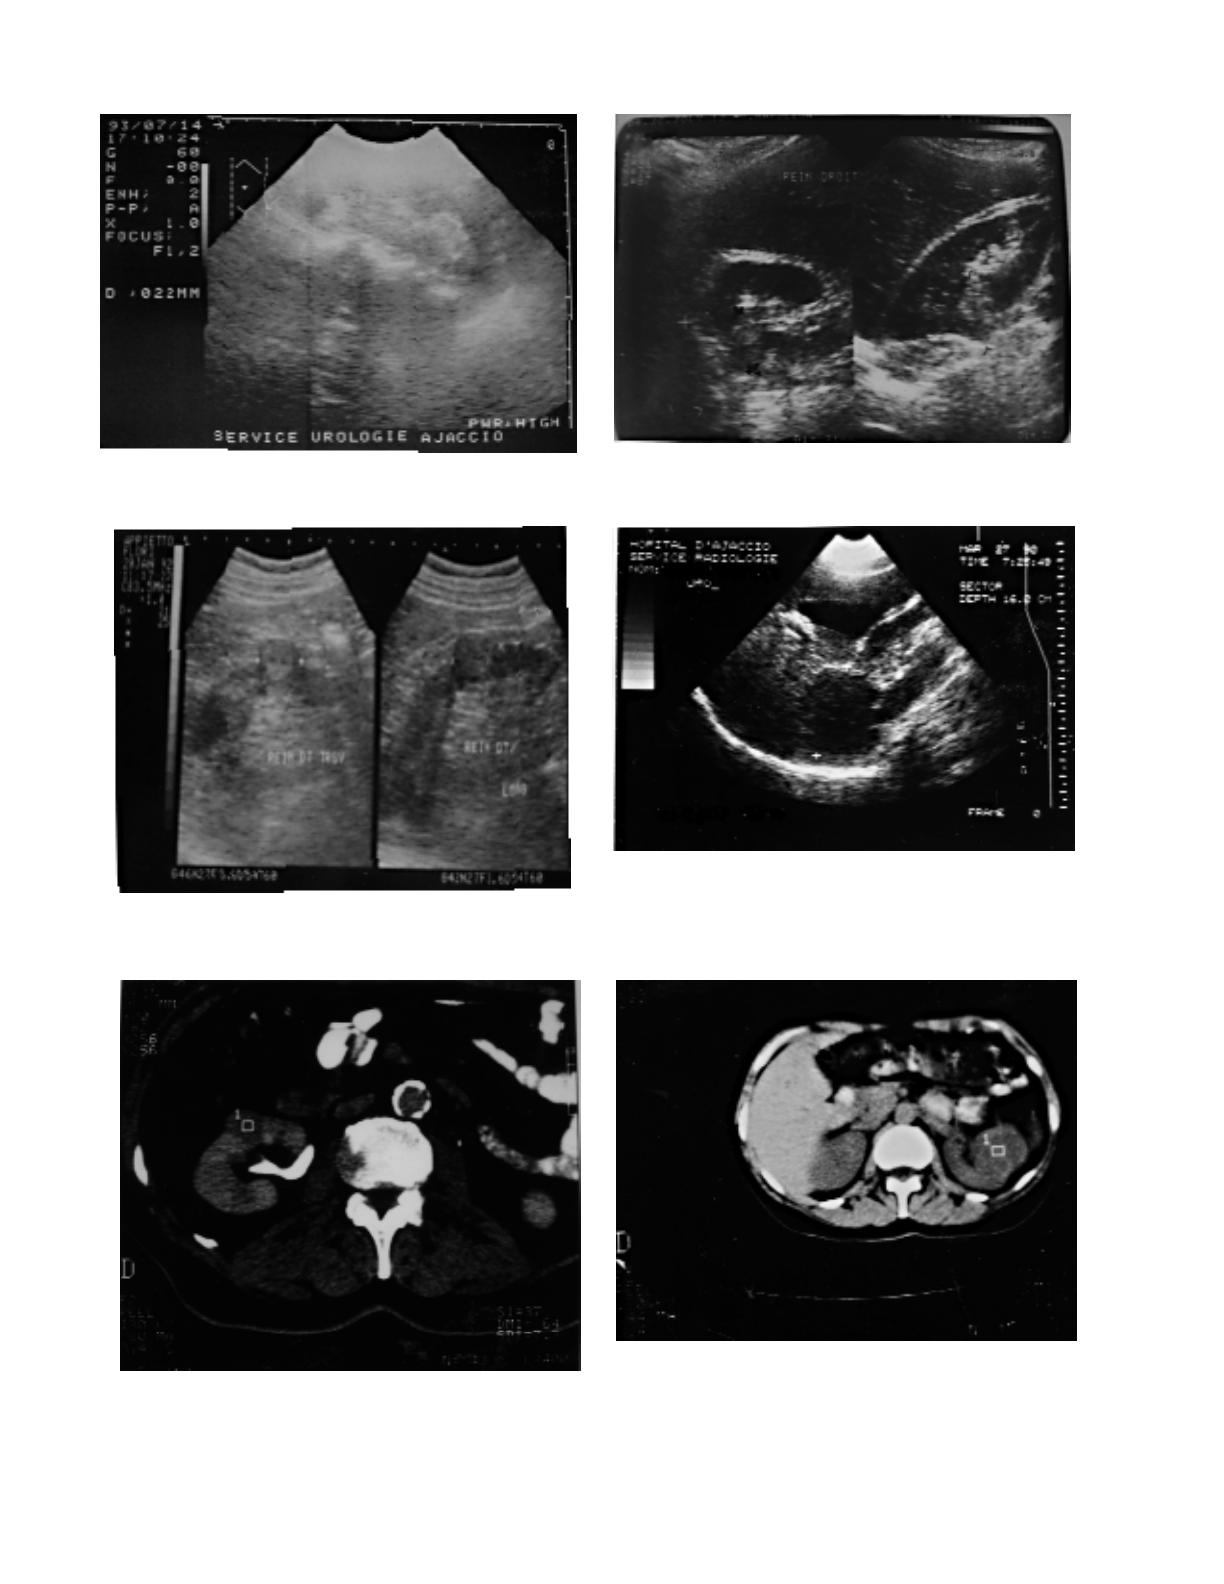

R é s u l t a t s : La découverte de la tumeur est écho-

graphique dans 68% des cas. Tous nos malades

ont été opérés permettant un examen anatomopa-

thologique de la pièce opératoire. Il s'agit de 14

cancers, 4 angiomyolipomes, 2 adénomes et 2

kystes hémorragiques (à contenu épais).

L'échographie met en évidence une tumeur hypo-

échogène dans 13 cas, 11 parmi eux sont des can-

cers, et hyper-échogène dans les 7 autres cas, dont

4 angiomyolipomes, 2 cancers, et 1 adénome. La

tomodensitométrie montre une tumeur hétéro g è-

ne dans 12 cas; tous, sauf un, sont des cancers.

Dans les 10 autres cas, dont 4 cancers, la tumeur

est homogène. L'artériographie montre une

tumeur hypervascularisée dans 3 cas, tous des

cancers, et hypovascularisée dans 7 cas : 2 can-

cers, 2 adénomes, 2 angiomyolipomes de très

petits volumes et un kyste hémorragique.

La découverte de la tumeur était échographique dans

16 cas (68,2%), urographique dans 2 cas, et scannogra-

phique dans 4 autres cas. Tous nos patients ont eu une

tomodensitométrie abdominale, et 20 d'entre eux ont

eu une échographie rénale. La plupart d'entre eux ont

eu une urographie intraveineuse et 10 ont bénéficié

d'une artériographie rénale. Une patiente a eu une biop-

sie percutanée échoguidée de la tumeur.